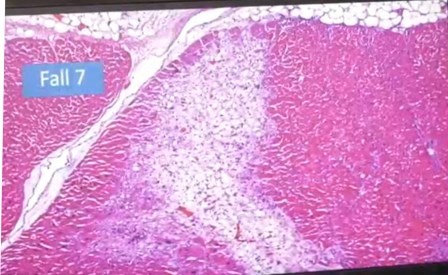

Atelectasis, pulmón colapsado

Aglomeración de linfocitos alrededor de un vaso

Esta aglomeración está en investigación

Vasos y endotelios, también en investigación, debido a la rareza, que les impide determinar lo que es

Esto no se pudo interpretar, son cosas “rarísimas” en este pulmón, y no solo una, sino varias veces, es decir, en varios fallecidos.